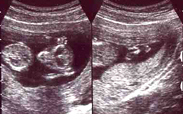

宇宙人!?

写真は左右に分かれています。

●左:頭部および胴体。

エイリアンの目のように見えるところは、目ではないそうです。

頭のてっぺん辺りらしいですが…。

両手をバンザイしています。

●右:お腹から足にかけて。

今度は位置が逆転していて、右の方に足があります。

よく分かりませんが、足を組んでいるそうです。

現在、身長は6cm。

そして頭の大きさが2cm。

まだまだ、ほとんど頭やね。